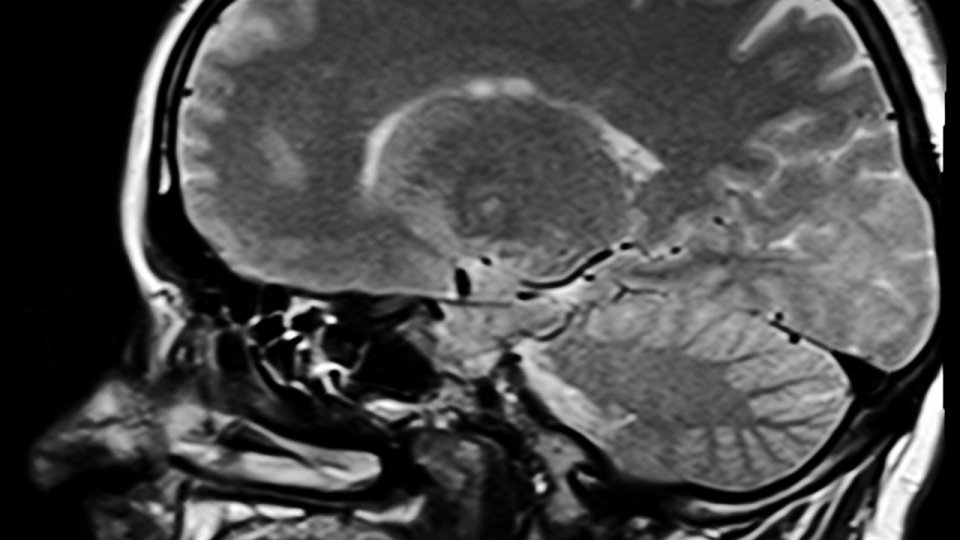

Spitalul Judeţean Timişoara anunţă o premieră medicală naţională care constă într-o procedură de tip hibrid neurochirurgicală şi de neuro-radiologie intervenţională la nivelul craniului.

Intervenţia a durat şase ore şi a fost efectuată de o echipă de patru medici specializaţi în neuro-radiologie intervenţională în colaborare cu echipa ATI P formată din dr. Loredana Luca şi Cristian Isoc. Acest tip de operaţii s-a efectuat o singură dată, în Franţa, la Spitalul CHU Bicetre, Paris, unde îşi desfăşoară activitatea dr. Cristian Mihalea. Acesta a introdus toate tehnicile de neuro-radiologie intervenţională în Spitalul Judeţean Timişoara, unde activează printr-o colaborare part-time, anunţă Spitalul Judeţean Timişoara. În urma intervenţiei, pacientul a evoluat favorabil şi este externat la domiciliu, cu un prognostic favorabil, deoarece riscul de sângerare datorită acestei fistule a fost exclus. Premiera marchează activitatea de 50 de ani de la înfiinţarea Spitalului Judeţean Timişoara şi 10 ani de la prima trombectomie din România, efectuată în august 2014 de o echipă formată din patru medici: Cristian Mihalea, Raoul Pop, Adrian Tutelcă şi Dan Mihoc Dan. De atunci, aici s-au efectuat 475 de proceduri cu o creştere semnificativă (25% pe an) a numărului acestor proceduri în ultimii patru ani.